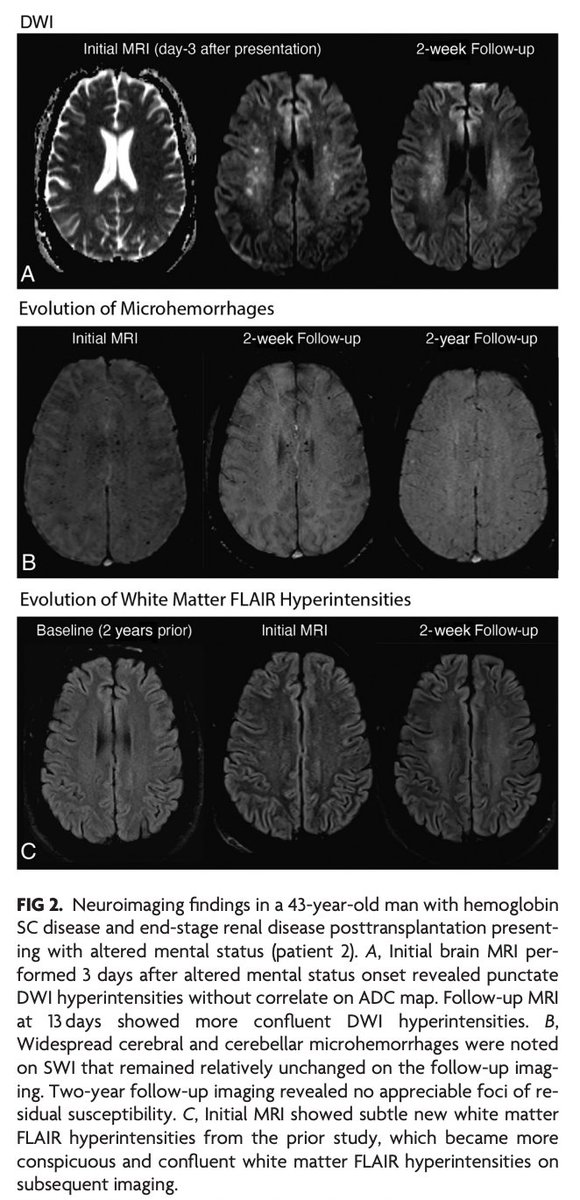

"Neuroimaging Findings in CHANTER Syndrome: A Case Series" #FellowsJournalClub #CHANTER WashUMedMIR Matthew S. Parsons | bit.ly/3QIeYZG

"Nontrauma-Associated Cerebral Fat Embolism Syndrome in Sickle Cell–Related Hemoglobinopathies: A Case Series and Systematic Review" doi.org/10.3174/ajnr.A… #FellowsJournalClub Ārash Nazeri; Helia Hosseini; Zack Nigogosyan, MD